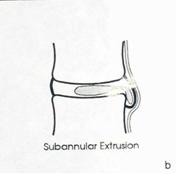

2 стадия — экструзия — выбухание в позвоночный канал элементов фиброзного кольца и дегенерированного пульпозного ядра;

— пролaпс — выпадение в позвоночный канал через дефекты фиброзного кольца фрагментов дегенерированного пульпозного ядра, сохраняющих связь с диском;

Экструзия (трансанулярная) с разрывом продольной связки: